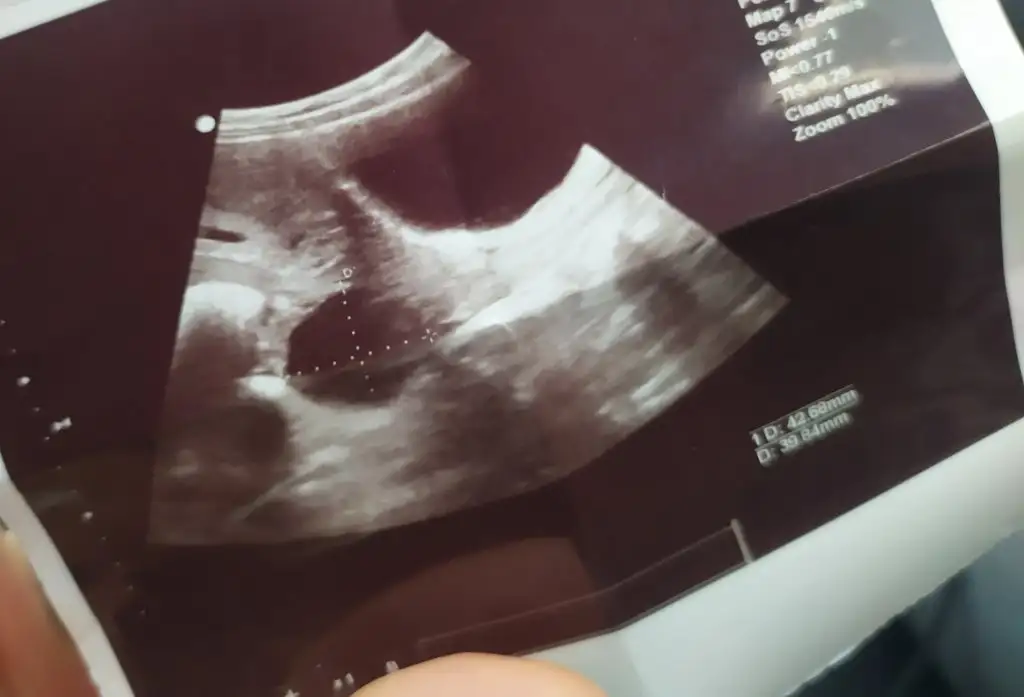

Atın resimleri bakalım doktorunuz sorun yok dediyse korkmayınKızlar hepinize merhaba 8 haftalık hamileyim. 2 gün önce kontrole gittiğimde kalp atışlarını duyduk, ve doktor ultrasonla baktığı sırada kistin var ama gebeliğe bağlı oluşan bir kist gibi, korkma gebelikte olur 12 14. Haftada geriler dedi. Şuan herşey yolunda dedi ve odadan çıkmadan ultrason görüntülerini verdi. Size sorum biraz sonra atacağım fotoğraflarda birinde bebeğim var, ve bebeğimi çevreleyen kese fasulye şeklinde. Fakat diğerini anlamış değilim. Bu yuvarlak şekil kist mi, yoksa gebelik kesesi mi? Ultrason aletini tutuş açısına göre kese şekli değişiyor mu? Bunun üstünden cinsiyet tahmini yapılıyormuş. Lütfen yardımcı olun ♥♥♥♥♥

Bilmiyorum ki, inşallah benzer durum tecrübe etmiş arkadaslarımız çıkar..Dediğiniz gibi fasulye şeklinde olan kese içinde bebeğiniz var diğer yuvarlaklar kist olmalı emin değilim yanlış bilgi olmasın kistse bu kadar büyük oluyormu

Ben boyutunu bilmiyorum canim.. bana kistin var gebeliğe baglidir 14. Haftalarda geriler dedi. Devlete kontrole gittiğimde söyledim, dr önemsemedi bile. Ama bakti tabiki ultrasonda inceledi. Tehlike taşısaydı mutlaka söylerdi bence. Korkulacak birsey yok gibiBende de aynı sorun çıktı malesef 6.5 haftalık hamileyim kist göründü 9.5cm büyük olduğu için doktor baya inceledi tümör marker testi istedi daha cıkmadı sonucum takip edeceğiz bu süreçte dedi aynı zamanda kistin burkulması, patlaması gibi riskleri olduğunu söyledi bebeğe bi zararı yok. Öyle bi durumda zaten kasıkta şiddetti bi ağrı olur direk acile gel dedi.